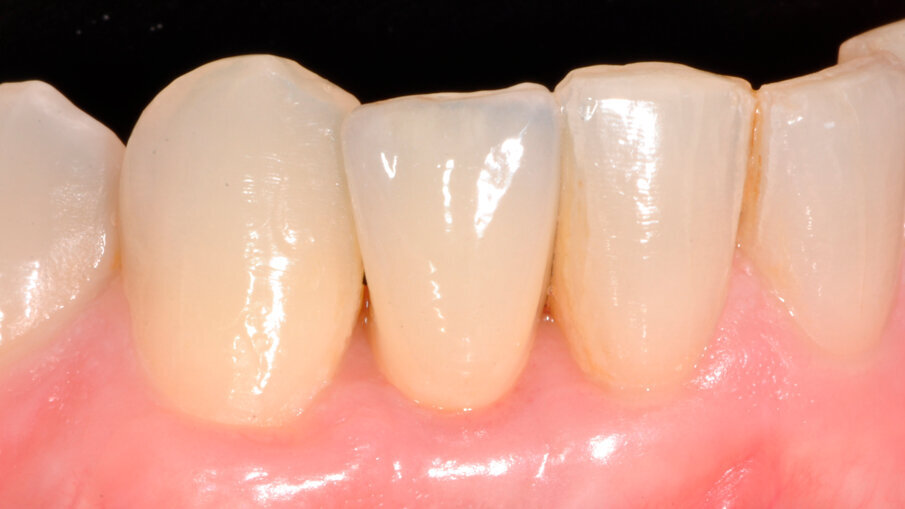

Pacient byl objednán na kontrolu týden po chirurgickém zákroku. V té době bylo dosednutí provizorní náhrady shledáno uspokojivým (obr. 11). Obrázek 12 zachycuje digitální plánování abutmentu Atlantis Crown Abutment ze zirkonu s adekvátním prostorem pro vrstvy keramiky. Definitivní náhrada byla vyrobena v zubní laboratoři s ohledem na dosažení harmonie se sousedními zuby (obr. 13). Byl také vytvořen prostor pro aproximální papilu. Abutment kotvený šroubkem s lingválním přístupem lze vidět na obrázku 14. Provizorní náhrada byla vyměněna za definitivní (obr. 15). Subgingivální část abutmentu poskytla oporu měkkým tkáním a byl zajištěn prostor pro mezizubní papilu. Atlantis Crown Abutment byl dotažen točivým momentem 25 Ncm (obr. 16). Lingvální přístup ke šroubku byl nejprve zakryt výplňovým materiálem (PTFE) a poté kompozitem. Následně byl pořízen další RTG snímek implantátu s upevněným definitivním abutmentem Atlantis Crown Abutment (obr. 17). Na obrázku 18 lze vidět konečný výsledek s definitivní náhradou, na němž je patrný adekvátní obrys měkkých tkání a vyplnění aproximálního prostoru. Keramika rovněž dokonale napodobila odstín sousedních zubů.